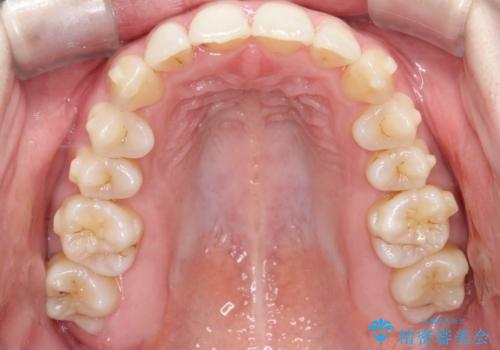

前歯のガタガタと欠損部を改善

- 患者様は、前歯のガタガタ(叢生)と左下5番の欠損部が気になるとのことで来院されました。診断の結果、インビザラインを用いて前歯の叢生を整えながら、左下5番の欠損部にはインプラント治療を計画しました。矯正治療により、歯並びを改善すると同時に、噛み合わせのバランスも向上させることを目標としました。矯正期間とインプラントの治療計画を並行して進めることで、患者様のご希望に応えるプランを立てました。

前歯の叢生改善のため、インビザラインによる透明で目立たない矯正装置を使用しました。治療中は、歯の移動による負担を最小限に抑えつつ、歯列全体のバランスを考慮して進めました。左下5番の欠損部には、矯正終了後にインプラントを埋入し、自然で機能的な咬合を回復しました。治療期間中、患者様には装置の正しい装着と日々の清掃を徹底していただき、歯肉やインプラント周囲の健康を保つようサポートしました。結果として、美しい歯並びと快適な噛み合わせを両立させることができました。